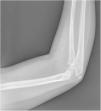

We present the case of a boy aged 9 years with no history of interest. He presented with a blotch of purple skin discoloration in the right arm that he had from birth and had grown since. The area had become tender in the past month. The salient findings of the examination were the presence of a rubbery, tortuous purplish lesion extending from the first digit of the right hand to the periaxillary region, spanning the ventral surface of the arm and forearm (Fig. 1). In the antecubital region, where the lesion was largest, there were several firm nodules tender on palpation. Since there was a delay for the ultrasound, a radiograph was performed that revealed several calcifications corresponding to the painful spots in the patient’s arm (Fig. 2). The ultrasound findings were consistent with a low-flow lesion. Laboratory tests evinced elevation of D dimer. The patient received a diagnosis of venous malformation with phleboliths and started treatment with acetylsalicylic acid at a dose of 50 mg/day, which was discontinued one month later, once the pain resolved.

Venous malformations are low-flow vascular malformations associated with phleboliths due to the stagnation of blood blow and localized thrombotic changes.1,2 Phleboliths result from the dystrophic calcification of clots. Their presence on imaging is a key finding in the differential diagnosis with other vascular and nonvascular conditions.1,3 Furthermore, their easy detection with a quick and noninvasive test, a plain radiograph, allows early diagnosis, thus contributing to better outcomes.1,2